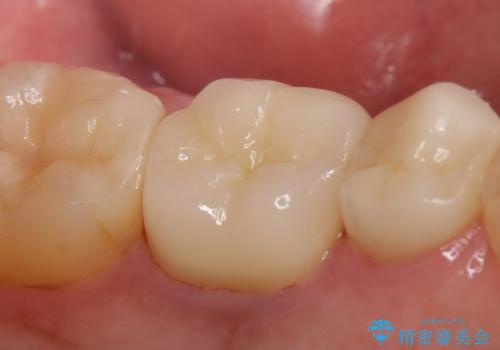

今回用いたオールセラミッククラウンはジルコニアフレームという白い素材の上にセラミックを盛っているため、審美性が非常に高いのが特徴です。

また、ジルコニアは人工ダイヤモンドの材料にも使われているほど高い強度を持っており、そのためオールセラミッククラウンは審美性だけでなく、奥歯やブリッジの補綴も可能とするクラウンです。